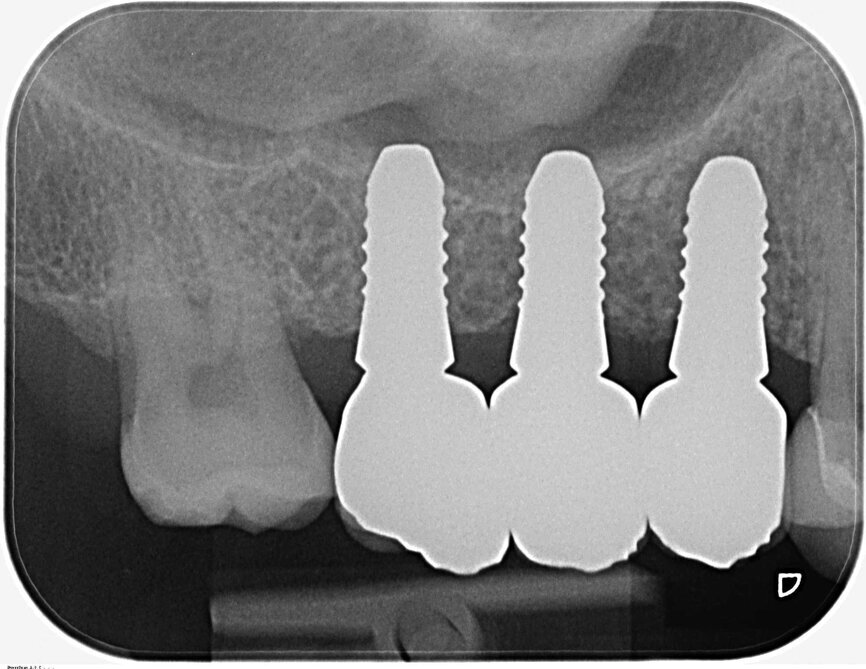

Fig. 20 : Radiographie de contrôle.

Fig. 25 : Radiographie de contrôle après l’insertion de la prothèse définitive. Il y a lieu de remarquer le défaut intra-osseux régénéré du côté mésial de la dent 18.

Les implants et la morphologie de la mâchoire ont été moulés pour la fabrication des piliers individualisés en zircone. La prise d’empreintes en technique à ciel ouvert a requis le dévissage des façonneurs gingivaux, de façon à permettre la mise en place de coiffes d’empreinte en PEEK. Une certaine expérience est nécessaire pour vérifier la précision de l’ajustement sur la radiographie de contrôle, car seule la périphérie du matériau est radio-opaque (Figs. 19 et 20).

Durant les visites de suivi, une et six semaines après l’insertion des restaurations implantaires tout-céramique, le tissu mou s’est avéré stable et sans irritation. La radiographie de contrôle a clairement montré la bonne ostéo-intégration des implants en céramique et la régénération du défaut osseux parodontal du côté mésial de la dent 18 (Fig. 25). Le patient s’est montré très satisfait de la réhabilitation globale de ses dents.